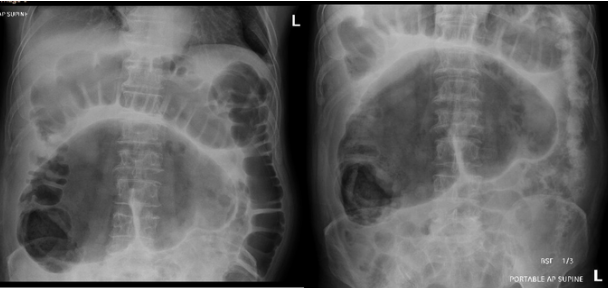

Cecal Volvulus

Jacob C Davis, DO

Mar 3, 2025

•

EndoCollab